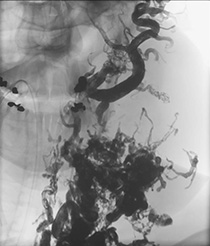

Die Behandlung von angeborenen Gefäßfehlbildungen am Universitätsklinikum Münster erfolgt in enger Zusammenarbeit der Klinik für Radiologie mit der Abteilung für Kinderchirurgie sowie der Klinik für Mund-Kiefer-Gesichtschirurgie. In einer gemeinsamen Spezialsprechstunde werden Patient*innen mit Gefäßanomalien durch alle erforderlichen Disziplinen untersucht und eine entsprechende Diagnostik wird eingeleitet. Für die nicht-invasive Diagnostik stehen in der Klinik für Radiologie sämtliche erforderlichen Geräte (Ultraschall, Magnetresonanztomographie, ggf. Röntgen) zur Verfügung. Die Therapie der Gefäßanomalien erfolgt im Anschluss entweder operativ, mittels Laser-Therapie oder bildgesteuert mittels minimal-invasiver Katheterverfahren.